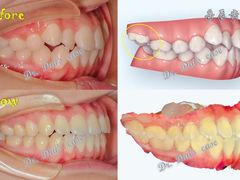

• 岳辰齿科(浦东长泰店)

• -岳辰齿科(浦东长泰店)

花栗鼠在魔都 | 22-08-17